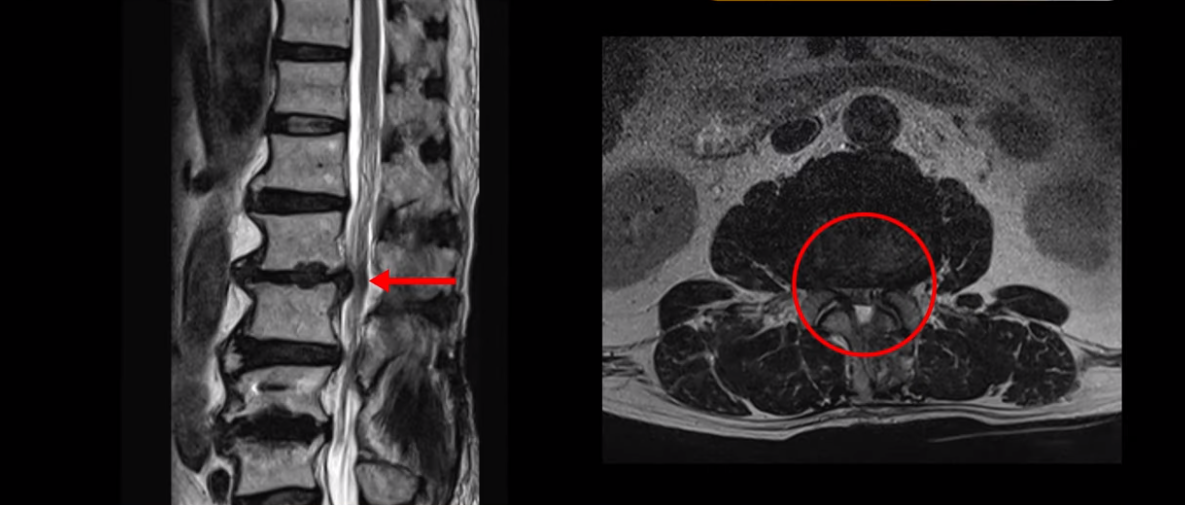

이분 허리 MRI를 보면서 간단히 설명드린 후 유합술 이후 인접마디에 문제가 생긴 환자분들이 왜 추가적인 수술을 서두르기보다는 허리기능을 살려주는 근육신경재활치료를 받는 게 좋은지, 또 치료는 어떻게 하는 게 좋은지 자세히 설명드리겠습니다. 이분 MRI를 보면 4번 5번에 나사가 박혀있습니다.

이렇게 나사가 박혀있으면 그 위나 아래에 문제가 많이 생기고 그걸 인접분절질환이라고 부릅니다. 이분도 유합술을 받은 그 윗마디인 2번 3번에서 디스크가 터져 밀려나와서 수술을 받았는데

이게 수술 후 사진인데도 여전히 척추관은 좁습니다.

나사 박은 마디 위쪽에 수술을 받았지만 수술 후에도 전혀 통증이 좋아지지 않고 다리에 힘도 빠져서 워커를 잡고 겨우 걷는 상태였습니다. 이렇게 유합술 이후 그 위나 아래에 문제가 생기는 인접분절질환은 모든 척추질환 중 가장 치료가 어려운 질환 중 하나로 꼽힙니다.

척추에 유합술을 해서 허리의 기능, 특히 근육의 기능이 많이 떨어진 환자들은 허리의 기능이 많이 떨어질수록 추가적인 수술을 해도 또다시 통증을 겪을 가능성이 높아집니다. 이런 통증을 척추수술 후 실패증후군, 또는 척추수술 후 통증증후군이라고 부릅니다. 허리의 기능이 많이 떨어질수록 수술로 신경 눌린 것을 잘 풀어줘도 여전히 아플 수가 있습니다. 이분도 역시 수술한 부분 위에서 디스크가 터졌다고 해서 수술을 받으셨는데 수술 후에도 통증은 똑같이 남아있습니다. 수술한 의사는 수술이 잘 됐다고 왜 아픈지 모르겠다고 하니까 환자만 답답한 겁니다.

그럼 이런 환자분들의 많이 약해지고 떨어진 허리의 기능을 어떻게 치료해서 통증을 없애줄까요? 허리의 기능에서 가장 많은 역할을 하는 것은 바로 근육입니다. 근육이 뭉치고 굳고 뒤틀림이 심할수록 허리의 기능이 떨어집니다. 허리기능이 떨어질수록 이런 허리의 퇴행이 심한 환자분들은 이미 신경구멍도 조금씩 좁아져 있기 때문에 신경눌림 증상도 생길 수 있습니다.